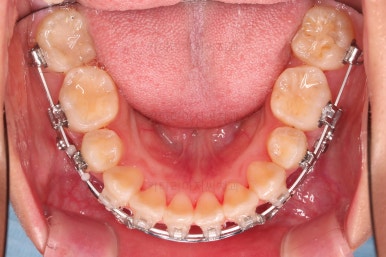

부산무턱교정치과 초진 시 입안의 모습입니다.

전반적으로 치열이 삐뚤고요. 아랫니가 윗니보다 뒤쪽으로 많이 가려져 있죠.

그래서 앞에서 봤을 때 아래 앞니가 거의 보이지 않는 상태인데요.

이런 교합을 "과개교합"이라고 표현합니다.

전반적인 교합, 치열, 과개교합, 튀어나와 보이는 앞니 등을 개선해줘야겠네요.

아랫니는 과개교합 개선을 위해 앞니 먼저 시작합니다.

아랫니가 매우 밑으로 많이 내려온게 보이시죠?

과개교합은 비교적 초반에 개선이 되었습니다.

아래 앞니의 높이가 개선된 뒤, 아랫니도 가지런하게 해줍니다.